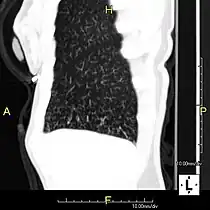

Oblique sagittal CT image showing lower lobe cylindrical bronchiectasis

Axial CT image showing chronic sinusitis in an individual with Kartagener syndrome